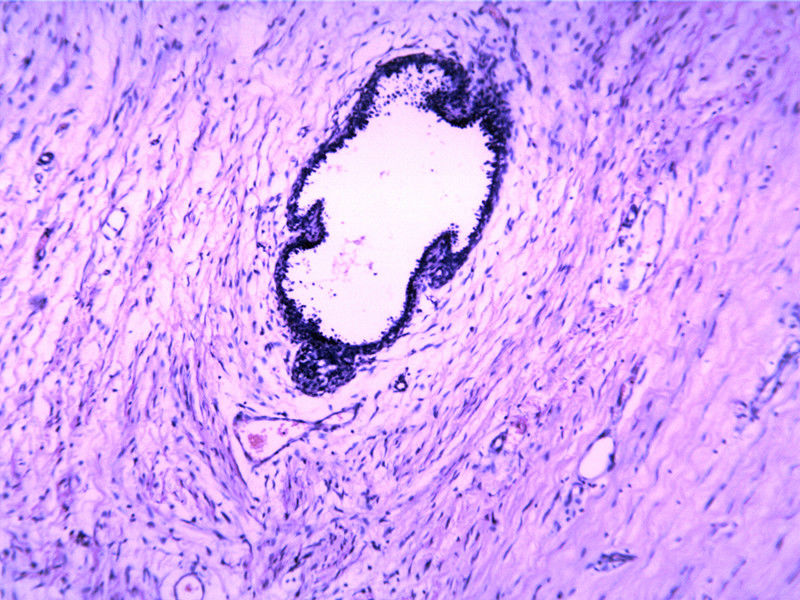

• 包块-无包膜(V4x3x3,79Y)图1

图1

• 包块-无包膜(V4x3x3,79Y)图2

图2

So far like a benign lesion. FA?